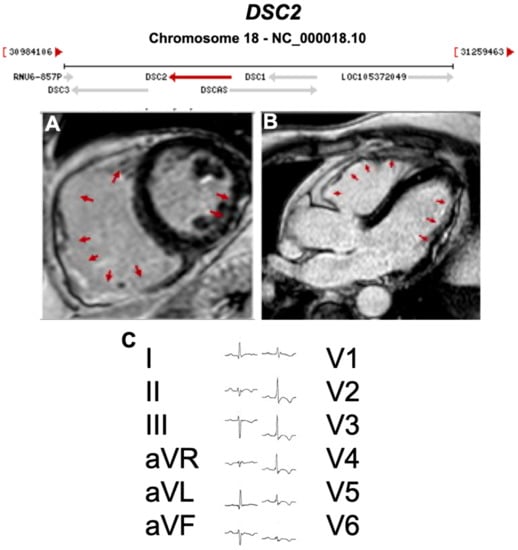

3.1. Desmosomal Genes

| DSC2 | Desmosome | 1–7% | AR | RV, BIV | ARVC11 | 18q12.1; 18 | Cardiocutaneous AR | Definitive for ARVC |